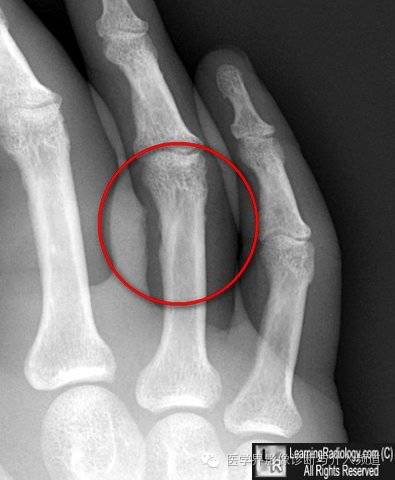

5、指骨血管沟:血管沟通常只见于骨皮质侧,呈对角线样走行。